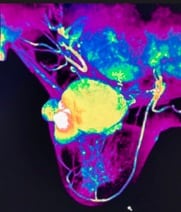

Imágenes por resonancia magnética (IRM) de mama. Una máquina de IRM utiliza un imán y ondas de radio para generar unas imágenes del interior de tu mama. Antes de una IRM de mama, te inyectan un colorante.

• Cáncer de mama por resonancia magnética